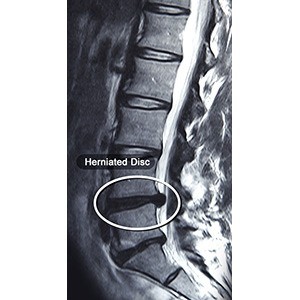

Lumbar Disc Herniation

Lumbar disc herniation is the most common cause of lower back pain and leg pain (sciatica). Aging, injury or trauma may cause the annulus fibrosus to tear, resulting in protrusion of the nucleus pulposus. This may compress the spinal nerves and/or spinal canal. The bulging disc may even break open, releasing the gelatinous material, which is a chemical irritant, causing inflammation of the spinal nerves.